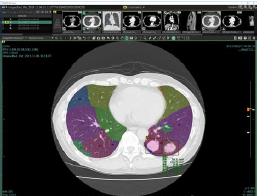

③ 「SYNAPSE SAI viewer」の新バージョンでは、左右合計18区域に分かれる肺区域を認識してラベリングができるようになったため、提示する所見文の候補に肺結節の場所を示す肺区域の情報を含めることが可能。

画面上で肺区域の確認が可能